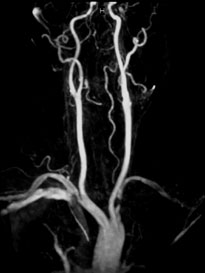

症例8 MRA

Bilateral CIA Stenting (Kissing stent with Palmaz stent)

ABI:右1.0 左0.6

【治療計画】